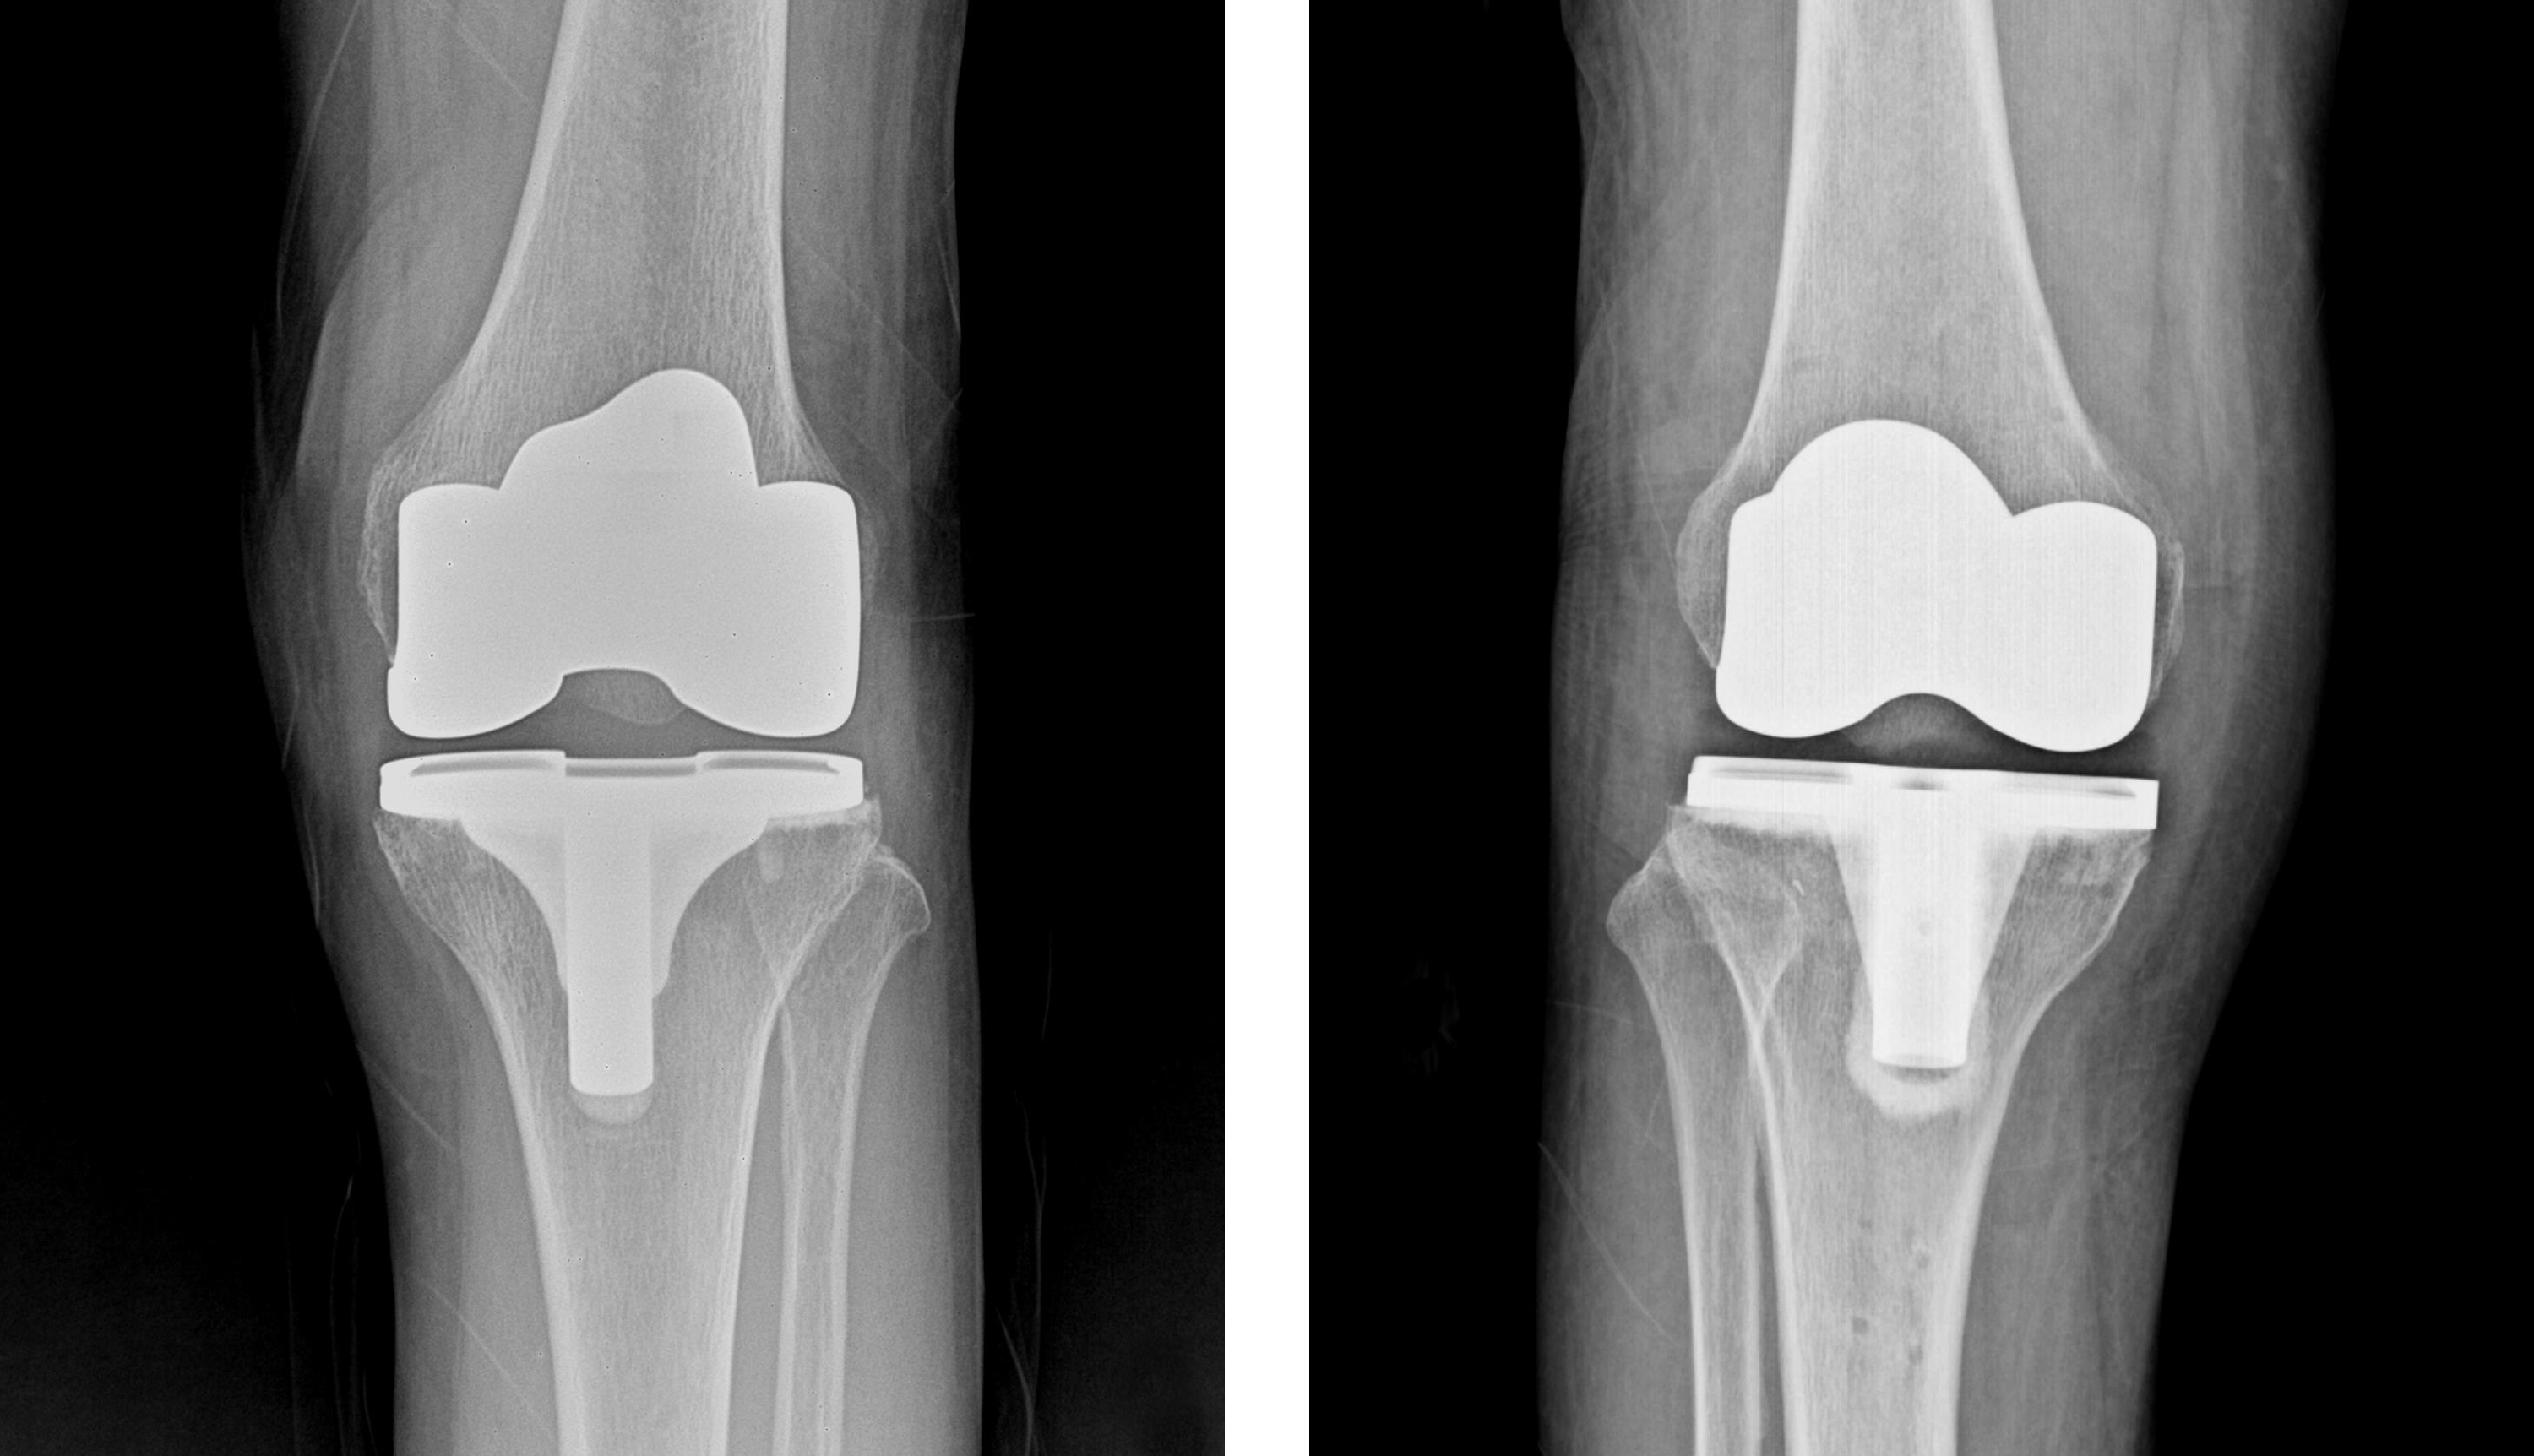

인공관절수술

관절 연골 손상이 심한 경우 인공관절수술, 관절내시경수술, 연골판재생술, 절골술, 줄기세포치료술 등의 수술적 치료를 시행합니다.